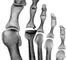

Диагноз устанавливают на основании характерных рентгенологических данных. Начальными рентгенологическими признаками являются уплощение и уменьшение размеров ядра окостенения ладьевидной кости. Костная ткань, особенно в субхондральных отделах, уплотняется. В дальнейшем ядро окостенения распадается на несколько фрагментов, имеющих различную форму и величину (рис. 1). Контуры фрагментов четкие или зазубренные. Прилежащие суставные щели расширены. Постепенно в течение 1—3 лет происходит восстановление структуры ладьевидной кости. Дифференцируют с туберкулезом, с замедленным и нормальным многоядерным окостенением ладьевидной кости.